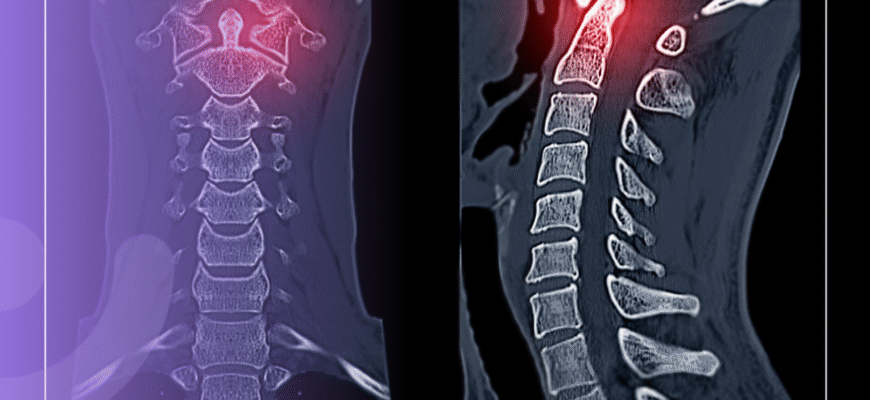

Хвороба Бехтерєва, відома також як анкілозуючий спондиліт, — це захворювання, яке змушує питати себе: що робити, коли тіло ніби відмовляється тебе слухатися?

Фундаментальність цієї недуги полягає в ураженні осьового скелета. Уявляйте: хребет, який перетворюється на нерухомий стовп. Немає гіршого відчуття, ніж безпомічність. Без стабільності в тілі важко знайти її в житті.